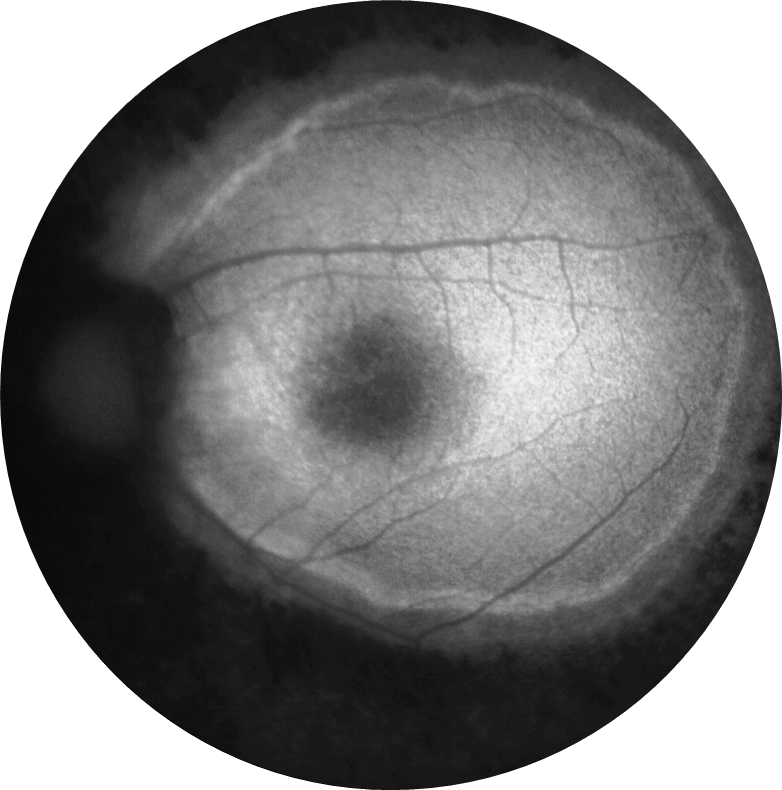

Kliniğimize her iki gözde çocuk yaştan bu yana gittikçe artan görme azlığı şikayetiyle 29 ve 21 yaşındaki iki kardeş başvurmuştur. 29 yaşındaki kardeşin her iki gözde görme keskinliği 3 mps düzeyinde iken 21 yaşındaki kardeşin 0,2 düzeyindedir. Hastaların her iki göz fundus otofloresans görüntülerini görmektesiniz. Bu bulgulara göre tanınız nedir? Lütfen cevabınızı aşağıya yazınız.

Bu ay size her iki gözde çocuk yaştan bu yana gittikçe artan görme azlığı şikayeti olan 29 ve 21 yaşındaki iki kardeşin fundus otofloresans görüntüleri eşliğinde tanılarını sormuştuk.

Tanı: Retinitis pigmentosa ’dır.

Retinitis pigmentosa (RP), tipik olarak orta-periferde başlayıp makula ve foveaya doğru ilerleyen, retinanın ilerleyici dejenerasyonunu içeren bir hastalık sınıfıdır. Tipik semptomlar arasında gece körlüğü, ardından görme alanının azalması, tünel görüşüne ve sonunda yasal körlüğe veya birçok durumda tam körlüğe yol açması yer alır. Retinitis pigmentoza (RP) yaklaşık olarak her 4000 kişiden birinde teşhis edilmektedir ve dünyada en sık görülen kalıtsal retina hastalıklarından biridir. Rod fotoreseptörlerin dejenerasyonu ile karakterizedir.

RP hastalarında, otofloresan görüntülemede zamanla daralan ve hastalık ilerlemesinin bir belirteci olarak hareket eden bir hiperotofloresan halka ortaya çıkabilmektedir. Bu halkanın dış sınırının içindeki fotoreseptöre atfedilen katmanların nispeten korunduğu, halkanın dış sınırının dışında ise elipsoid bölge ve dış limitan membran kaybı ile fotoreseptör katmanlarının incelmesi ve dış nükleer katmanın incelmesi veya yokluğu gözlemlenebilmektedir.